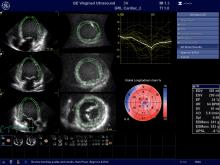

VIDEO: AI-Assisted Automatic Ejection Fraction for Point-of-Care Ultrasound